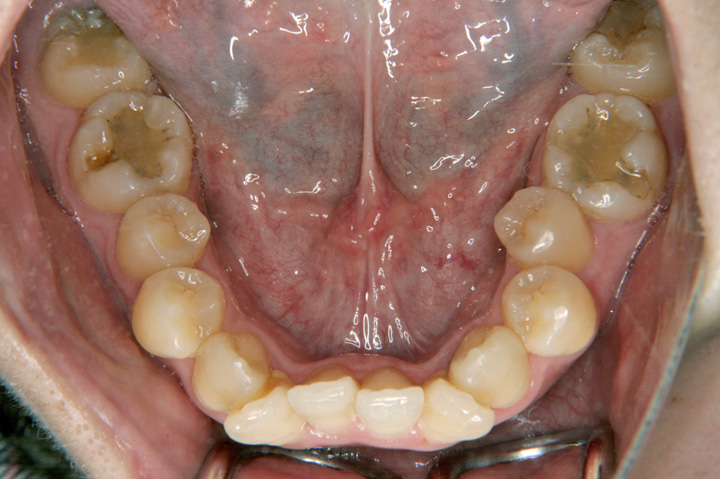

前歯のデコボコを気にされて来院された成人の女性です。叢生と前歯の傾斜の改善のため、上下顎小臼歯を抜歯と、上顎両側大臼歯不正のため、大臼歯抜歯もさせていただきました。エッジワイズ装置を用いて歯並びを整えました。エシックスとボンデッドワイヤーとリテーナーを併用した保定に移行しております。

初診時

動的治療終了時